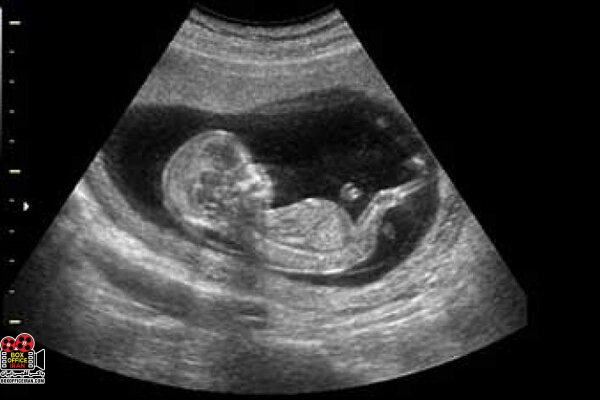

کارگردان «جادههای برقی» در توضیح این مساله که چرا سونوگرافی باعث افزایش تعداد نوزادان پسر شده است، بیان کرد: خانوادههایی که به دنیا آمدن فرزند پسر برایشان بسیار مهم است، وقتی در سه ماهگی یا ۲ ماهگی متوجه جنسیت جنین دختر خود میشوند، به راحتی به سمت سقط میروند یا از طریق رژیم غذایی، تزریق آمپول یا کاشت تخمک به پسر شدن فرزندشان کمک میکنند. این مستند موضوعمحور به تعیین جنسیتی اشاره میکند که به دست بشر افتاده و عامل نابود شدن موازنه جنس جنین در جهان است.

وی تاکید کرد: در این مستند قرار بود یک زن حضور داشته باشد؛ او برای تعیین جنسیت فرزند پسرش به پزشک مراجعه میکرد، من از ابتدای تصمیم او برای گرفتن رژیم غذایی مناسب، انجام سونوگرافیها و خرید داروها با او همراه شدم و تمام هزینههای معالجهاش را برعهده گرفتم به شرطی که با ما در طول ساخت مستند همراه باشد اما به دلیل مخالفت همسرش، بعد از سه ماه از همراهی با پروژه منع شد تا اگر نوزاد دختر باردار بود، بدون دخالت هر کسی آن را سقط کند.